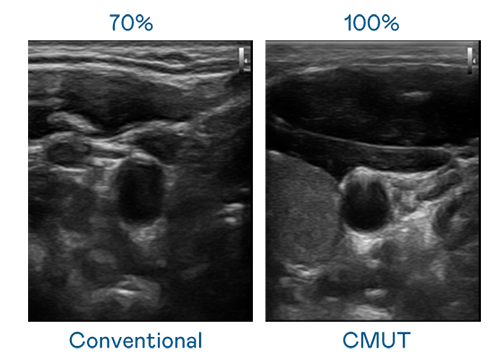

CMUT 技术是一种用电容式微机电元件来产生超音波讯号的技术。与传统 PZT 压电式技术相比,CMUT 频宽增加 30%,更宽频的超音波讯号让影像解析度大幅提升,是实现高影像品质医疗超音波扫描、促进精准医疗发展的关键技术。

大频宽带来超清晰影像

超音波影像的解析度高低,首先取决于探头能发出的讯号频宽。918搏天堂 CMUT 可提供高清晰的超音波讯号,提供高频宽、高灵敏度、影像纹理细节更高的超音波影像,协助医护人员缩短影像判读时间及利用精准的医疗影像进行诊断。